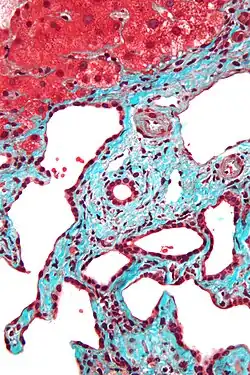

Histopathology of a bile duct hamartoma, high magnification, H&E stain. It shows typical features of bile duct hamartoma: Small to medium sized, irregularly shaped bile ducts lined by bland cuboidal epithelium (may also be flattened). Prominent intervening collagenous stroma. Bile ducts containing eosinophilic debris (may also contain inspissated bile) -

Micrograph of a bile duct hamartoma. Trichrome stain, high magnification -